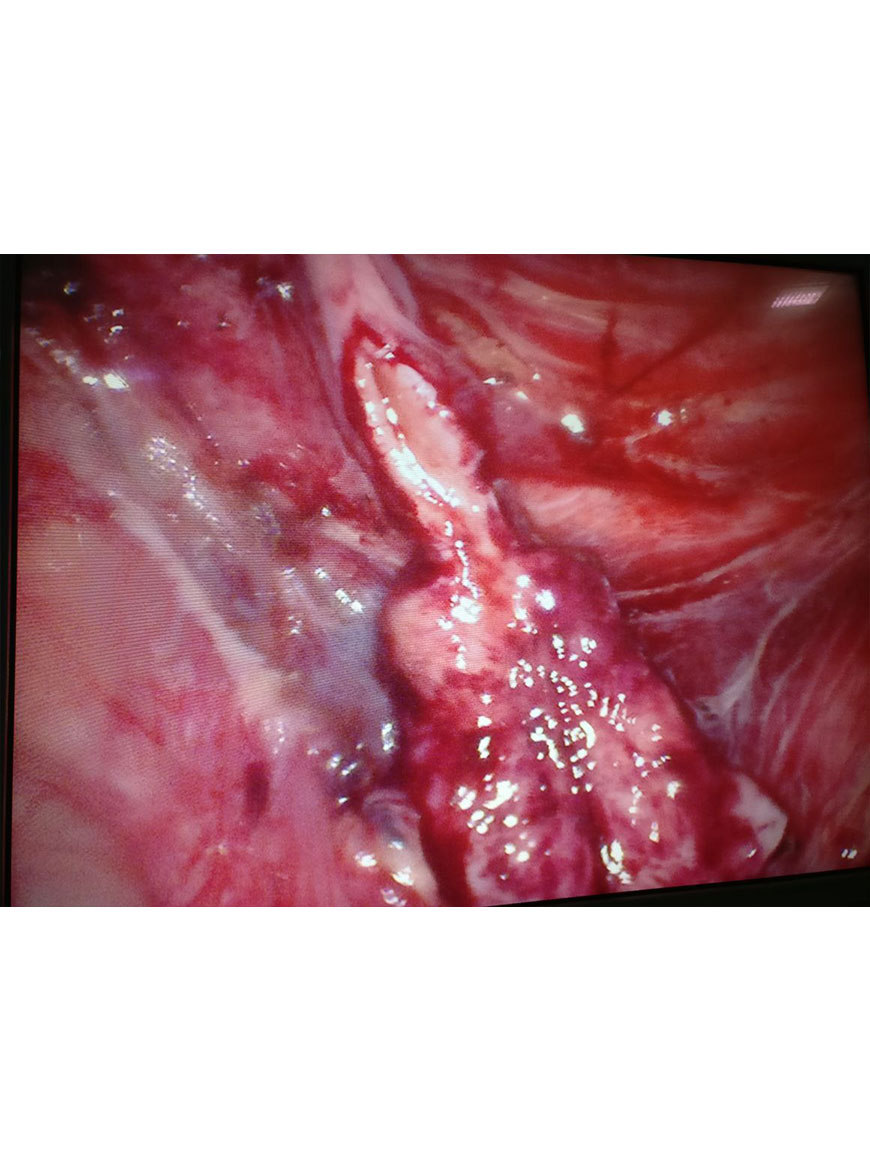

Radical Nephrectomy